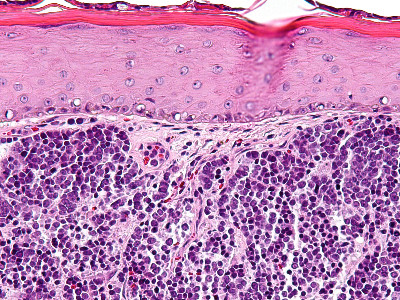

PA:

In de dermis, soms reikend tot in subcutis zijn velden van kleine ronde tumorcellen te zien (‘small blue round cells’). De tumorcellen zijn meestal gerangschikt in nesten, platen of strengen (trabekels). Soms worden ‘Homer-Wright pseudo-rosetten’ gezien, dat zijn kransen van tumorcellen rond een centrale zone gevuld met neurofibrillair materiaal, typerend voor neuro-endocriene tumoren. De tumorcellen zijn klein tot middelgroot en hebben zeer weinig cytoplasma en grote kernen t.o.v. de hoeveelheid cytoplasma. De celkernen vertonen een karakteristiek ‘salt and pepper’ chromatinepatroon (fijnkorrelig chromatine) met onopvallende nucleoli. Er zijn vele mitosen te zien. De tumor kleurt aan met cytokeratine 20 (CK20) en met neuro-endocriene markers (chromogranine A, synaptofysine, CD56). TTF (positief bij longcarcinoom) en S100 (positief bij melanoom) zijn negatief. Bij ongeveer 80% van de gevallen kan het Merkelcel-polyomavirus in de tumorcellen worden aangetoond.

ingescande coupe (zoom) |

Bron

hoge resolutie PA-foto: Kevin Kwee en Afdeling Pathologie MUMC. Klik

op de afbeelding om in te zoomen.